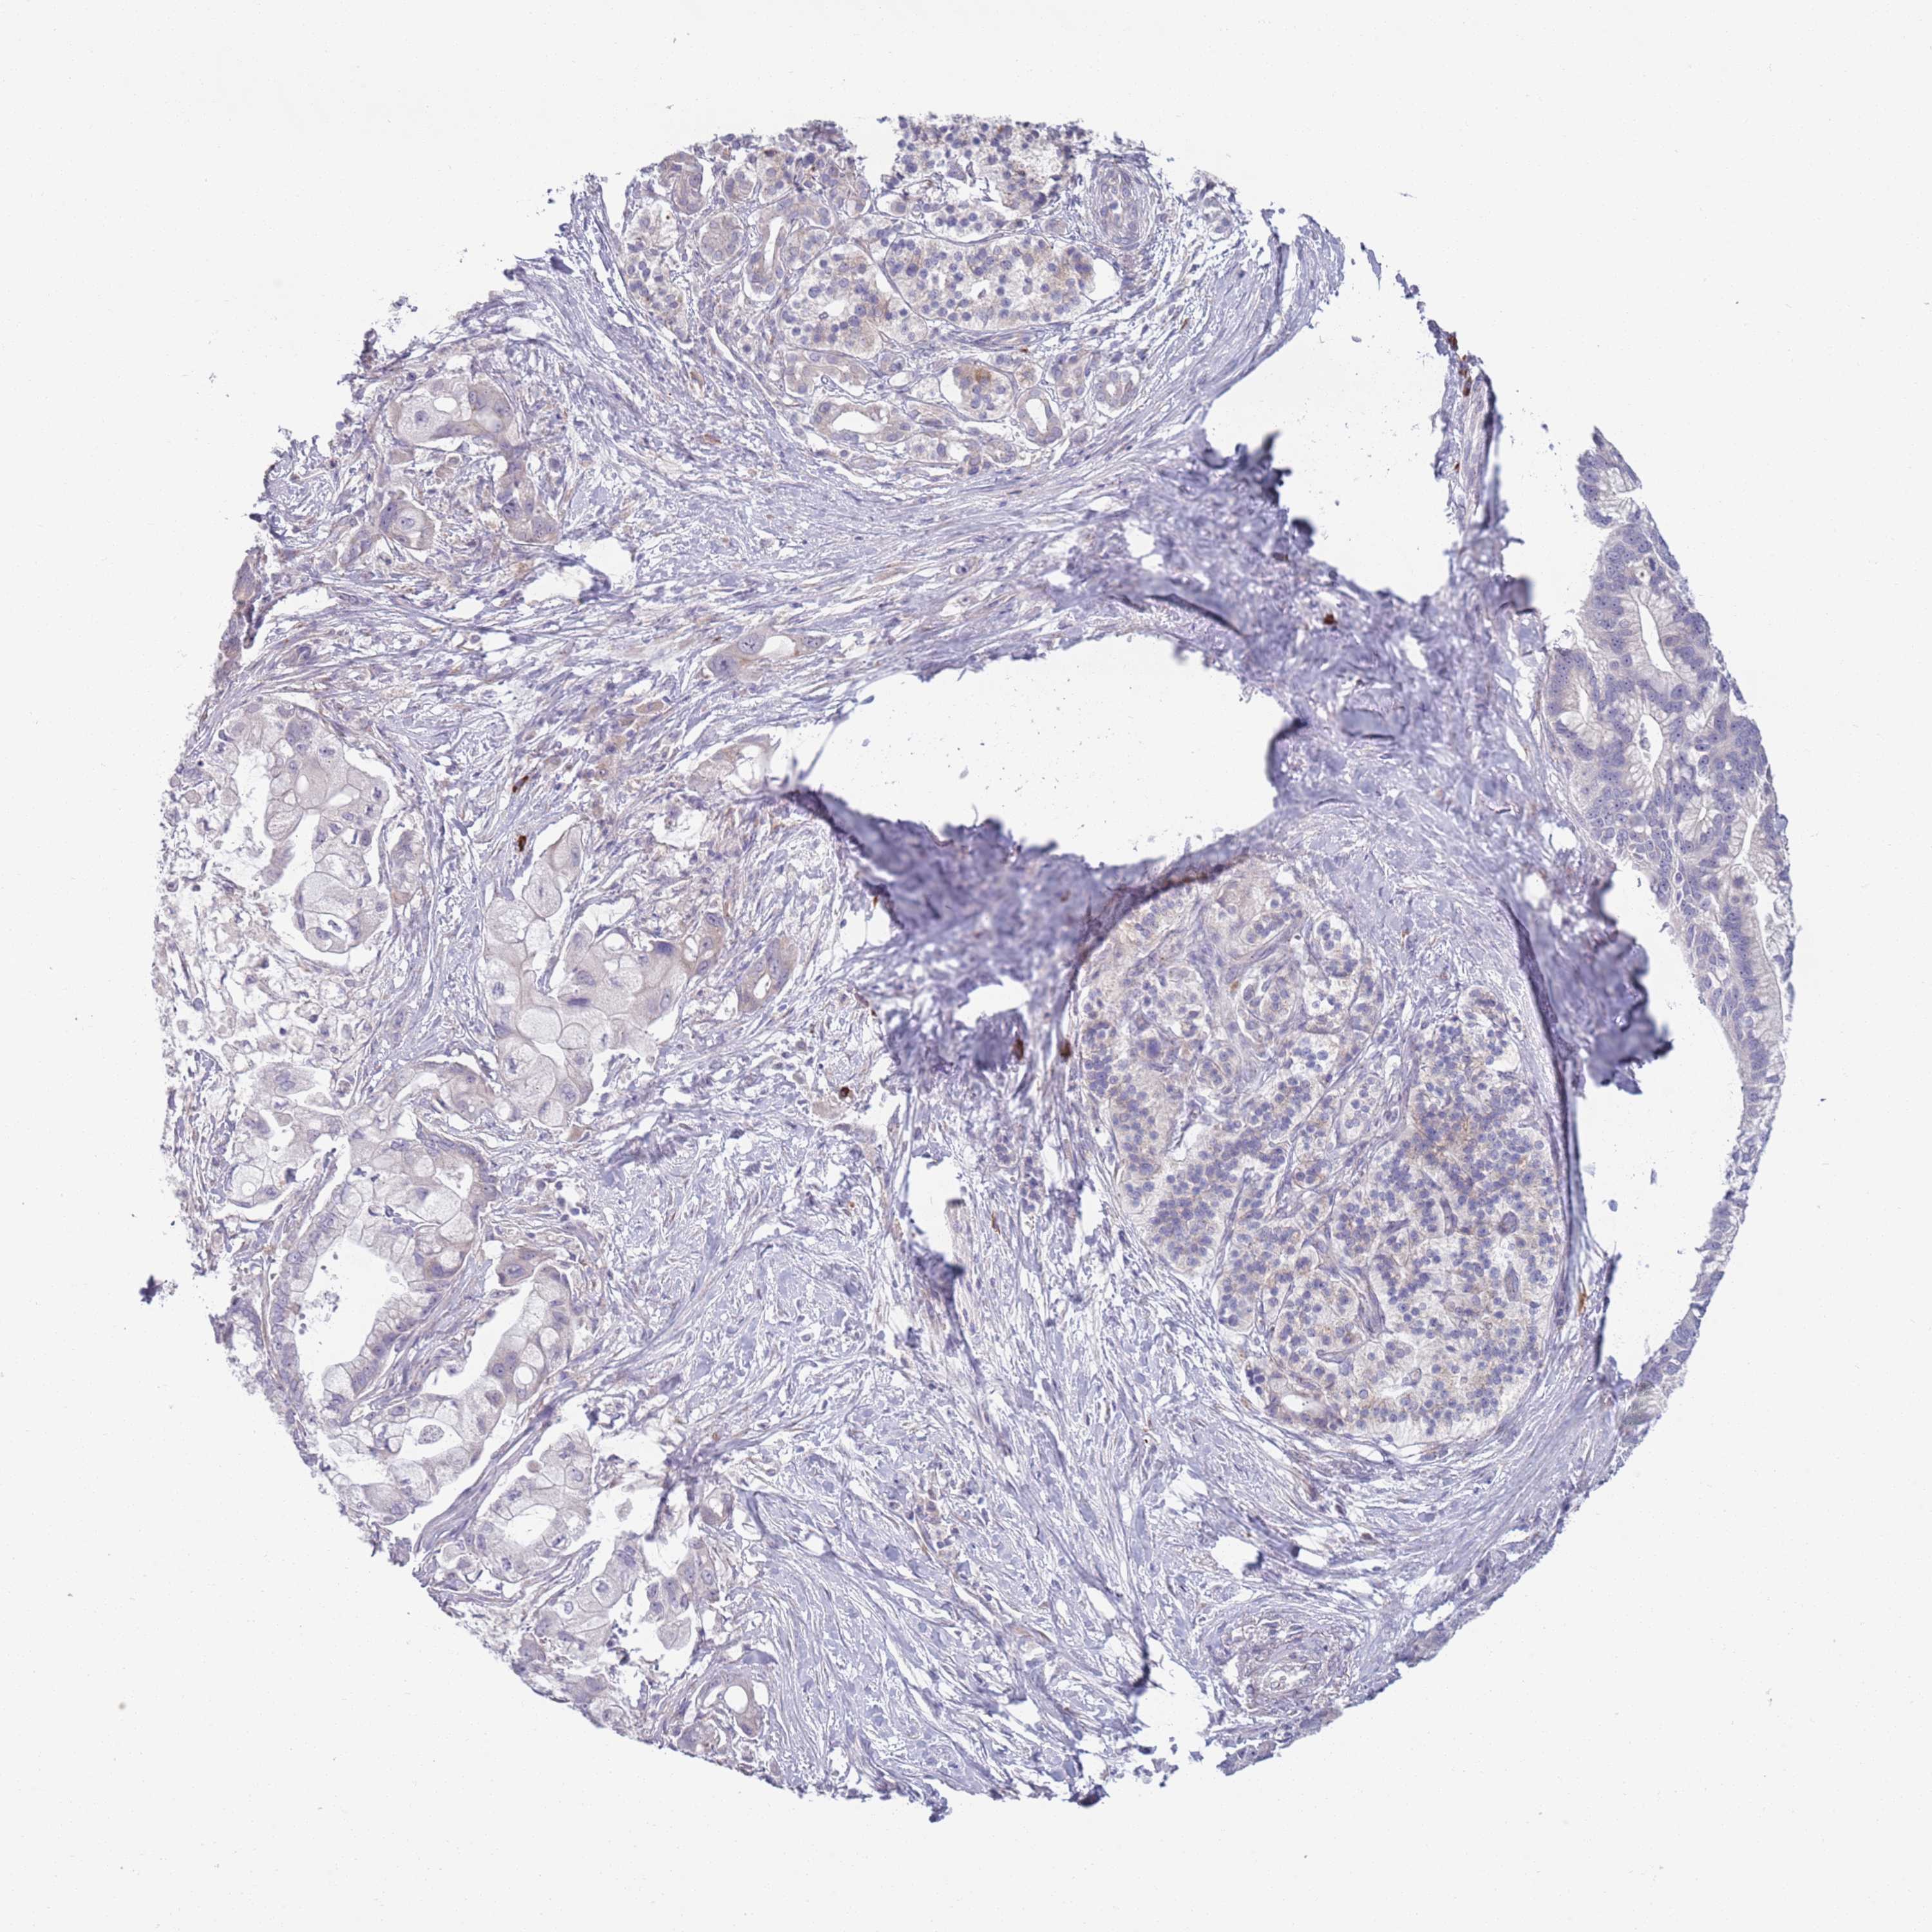

PANCREATIC CANCER - Protein expressioni

A mouse-over function shows sample information and annotation data. Click on an image to view it in a full screen mode. Samples can be filtered based on level of antibody staining by selecting one or several of the following categories: high, medium, low and not detected. The assay and annotation is described here.

Note that samples used for immunohistochemistry by the Human Protein Atlas do not correspond to samples in the TCGA dataset.

Antibody stainingi

Antibody staining in the annotated cell types in the current human tissue is reported as not detected, low, medium, or high, based on conventional immunohistochemistry profiling in selected tissues. This score is based on the combination of the staining intensity and fraction of stained cells.

Each image is clickable and will lead to virtual microscopy that enables deeper exploration of all samples and also displays staining intensity scores, fraction scores and subcellular localization as well as patient and tissue information for each sample.

Antibody HPA048884

Staining

High

Medium

Low

Not detected

Intensity

Strong

Moderate

Weak

Negative

Quantity

>75%

75%-25%

<25%

None

Location

Nuclear

Cytoplasmic/membranous

Cytoplasmic/membranous,nuclear

Adenocarcinoma, NOS